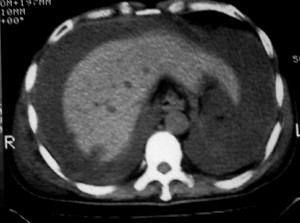

m ,60岁,右上肺ca术后一月。

右侧肺癌术后:肝内可见多个大小不等的低密度结节影。腹腔及双侧胸腔大量积液。考虑:肺癌并胸膜及肝脏转移。

腹水,肝及右肾多发低密度影。考虑转移。

肝及右肾转移瘤,双侧胸水

右肾及肝内多发转移瘤,胸水。

1、右肺癌术后改变。2、双侧胸水、腹水。3、多发性肝囊肿,右侧肾囊肿。

目前转移或复发的依据不足,术后才一个月,个人认为还是让临床去判断,而且需结合术前常规检查,有无肝肾囊肿;另外有一个疑问:肝胃间隙内团状软组织影是胃食管交接区吗,胃腔太小了吧,有无手术史请楼主告知.